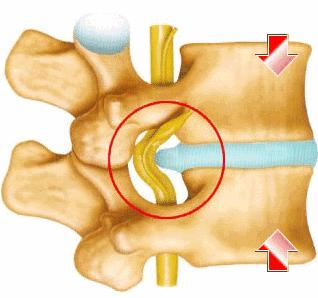

◎ 腰椎间盘突出症是一种腰椎间盘的退行性改变,由于纤维环的蜕变,破裂,导致髓核突出,继而压迫,刺激脊髓和神经根,最终出现下肢的神经压迫症状。/ 网络图片

“轻一点的情况,腰轻轻一动就不舒服,整体身体都感觉硬邦邦的,难以动弹;如果情况严重的,即便稍微一咳嗽,或者大小便稍一用力,腰部乃至整条腿都像电针扎样的疼痛感便接踵而来。”南方医科大学第三附属医院脊柱外科二区主任医师吴毅向39深呼吸形容,以腰椎间盘突出为例,它本质上就是一种神经性疼痛,这种对神经赤裸裸的压迫,严重时就像把自己的身上某一根筋用力扯出来,然后拿把刀使劲刮。

◎ 通过影像可见明显的腰椎间盘突出。/ 知乎